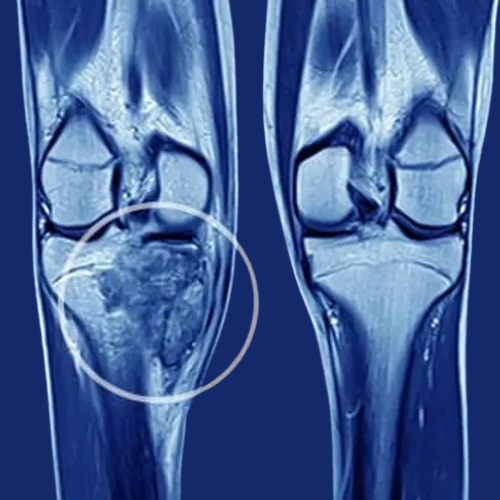

Knee pain due to knee arthritis can severely impact your daily life, making it difficult to walk, climb stairs, or even sleep comfortably. At Dr... Read More